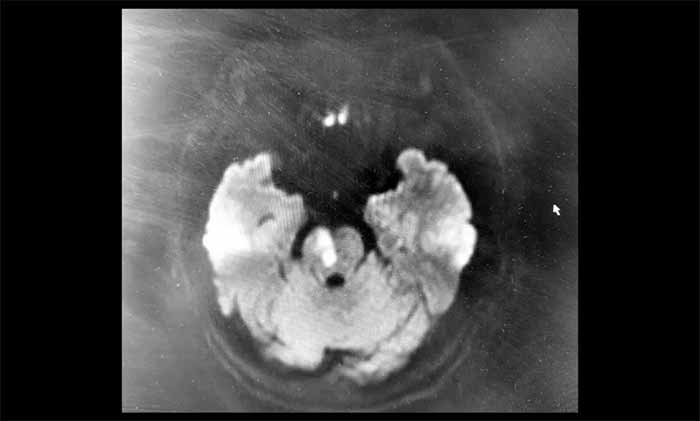

磁共振弥散加权成像(DWI)结果显示:脑干区域可见明确的斑片状高信号影,对应的ADC图呈低信号——这是新发脑干梗死的影像证据。脑动脉成像同时提示血管轻度硬化,右侧椎动脉V4段纤细。基于对后循环缺血的深刻认识和对影像细节的敏锐把握,潘登博士结合影像与临床症状,迅速明确了诊断,为患者争取了宝贵的治疗时间。

“这位患者症状看似轻微,但DWI影像显示脑干已发生急性缺血损伤。脑干结构精细、功能关键,即使小范围梗死也可能带来严重后果,或是更重症风险的前兆。”潘登博士说。

▲ 脑干梗死